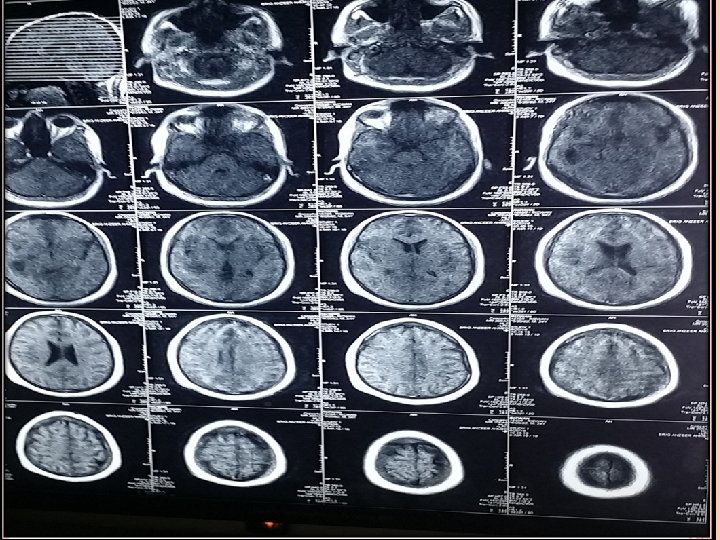

INVESTIGATIONS Blood Tests CBC (TLC-12000/u. L) CRP (3. 2 mg/L) ESR (28 mm/hr). Imaging CT scan Brain ( plain ) CT scan Brain with contrast. MRI Brain with contrast.

MRI T 1 : necrotic center ( hypointense) Capsule ( hyperintense) Edema ( hypointense) T 2 : necrotic center ( hyperintense) Capsule ( hypointense) Edema ( hyperintense)